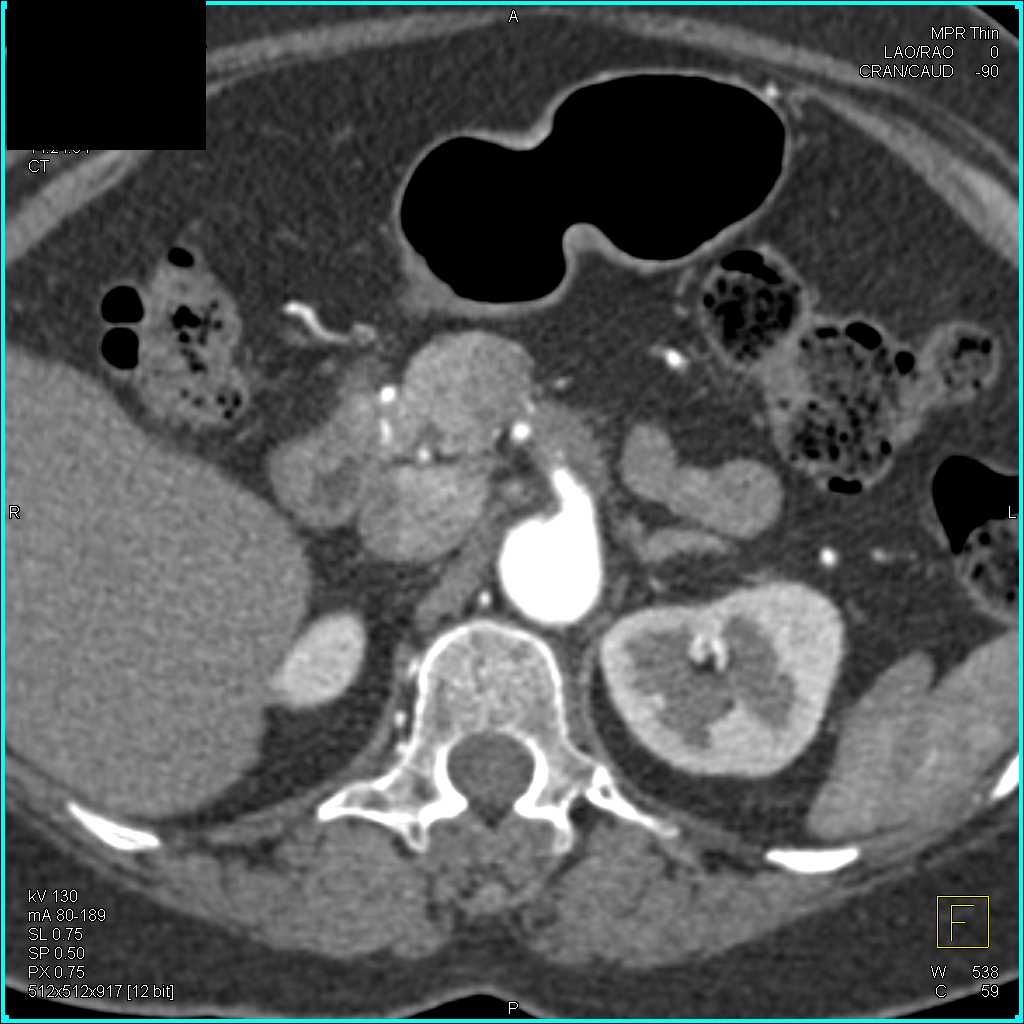

Neuroendocrine Tumor Body of Pancreas